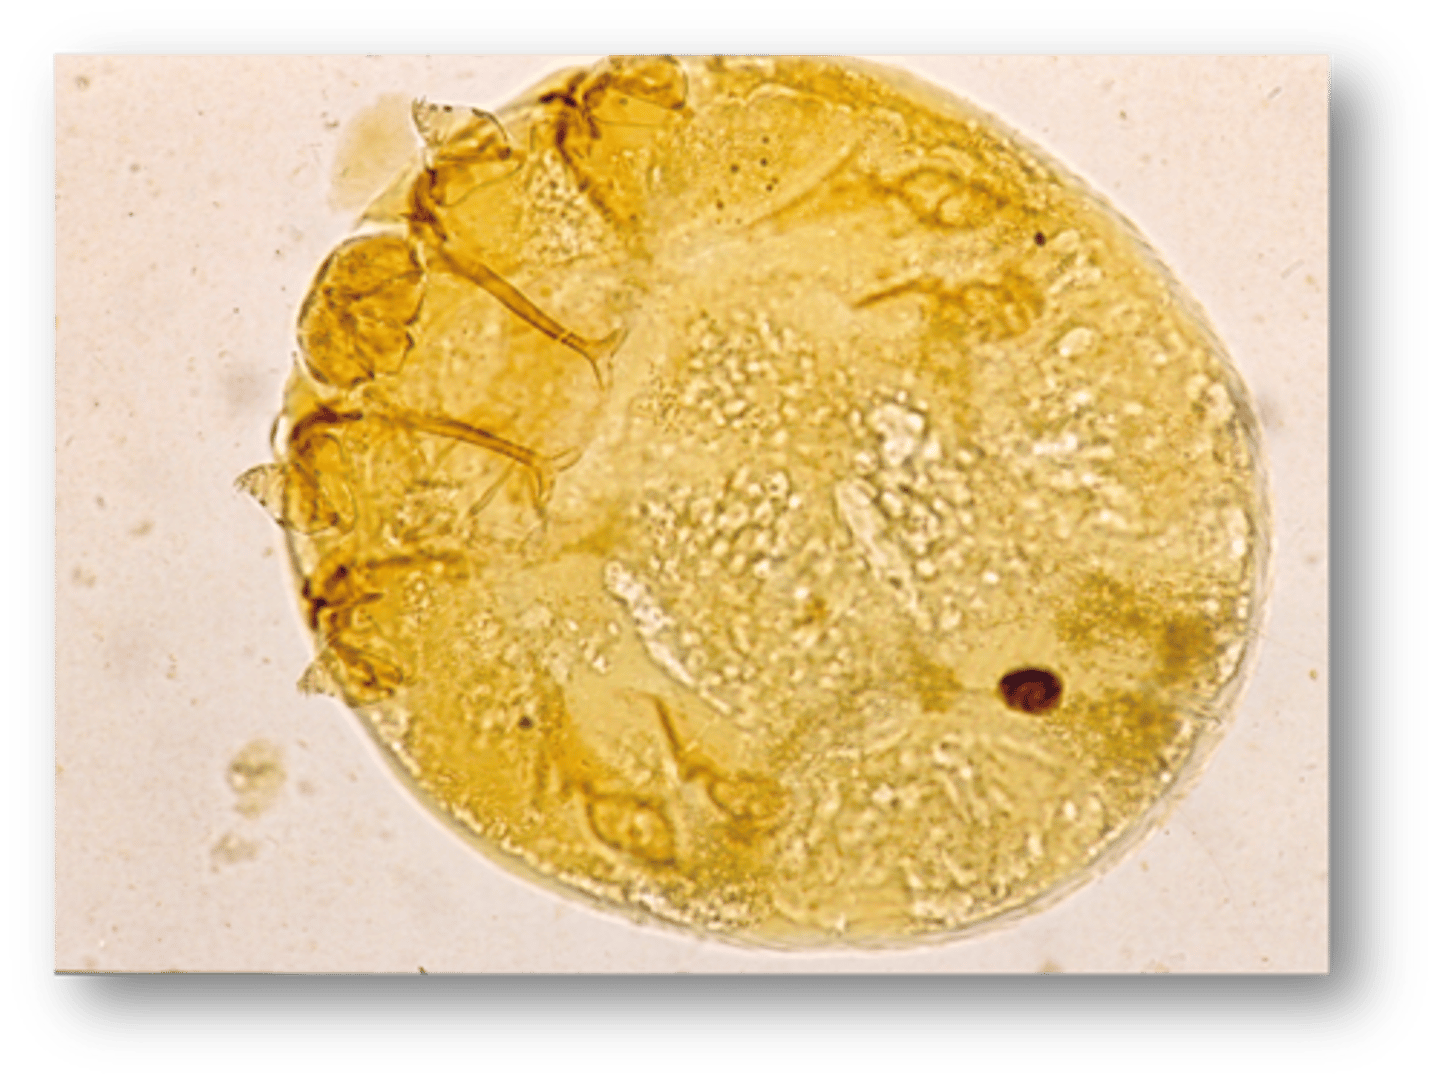

Slide from a dead chicken - What parasite and life stage is this?

Eimeria spp. - Merozoites (banana-shaped, central red nuclei)

Eimeria spp. - Microgametocyte (see many small microgamonts within cell)

Eimeria spp. - Schizonts (many merozoites within them)

Eimeria spp. - Macrogametocyte (see wall forming bodies)

Eimeria spp. - Sporulated oocyst (20 microns).